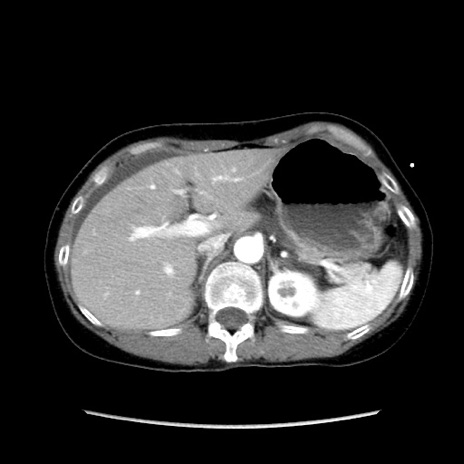

矢状断像